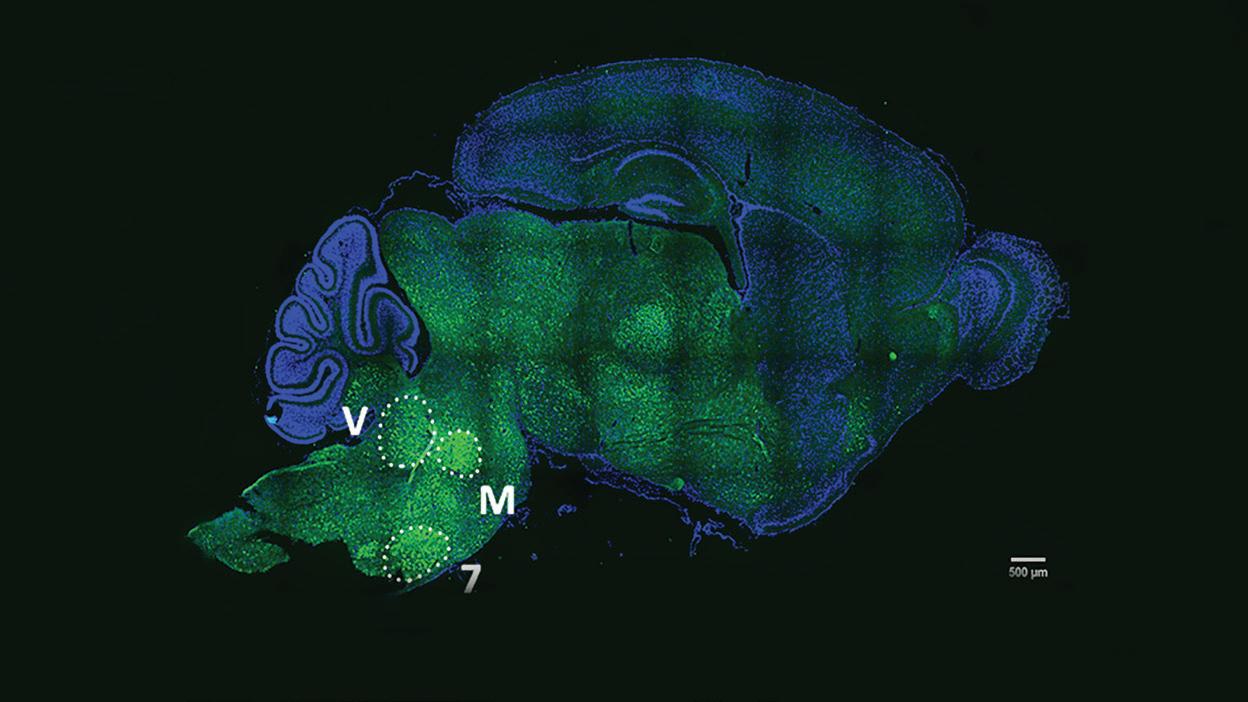

Techniques advanced by RUSH’s Bryan Killinger, PhD, are providing scientists with new ways of studying Lewy bodies, abnormal clumps of the protein alpha-synuclein in the brain that are a defining feature of Parkinson’s disease pathology.

Seeking an understanding of the disease process underlying Lewy pathology

The accumulation of Lewy bodies, or abnormal aggregations of the protein alpha-synuclein, in the brain is a hallmark of Parkinson’s disease and other neurodegenerative diseases. To study the disease process underlying the pathology of Lewy bodies, Bryan Killinger, PhD, applied for and received an R01 grant from the NIH. This study aims to determine Lewy pathology interactions in neurodegenerative diseases in the human brain and investigate Lewy pathology interactions in the rodent brain as neurodegenerative diseases develop. Mapping many more tissue samples from RUSH’s brain bank offers hope that cellular processes will be discovered that could shape new drug discovery efforts and better ways to study potential therapeutics in animal models of Parkinson’s disease.